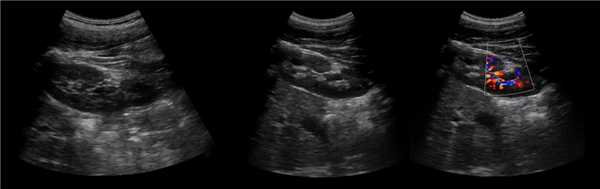

Бывает колонна Бертини врезается в центральную часть почки, разделяя ее полно или неполно на две части. Такая паренхиматозная перемычка — это паренхима полюса одной из эмбриональных долек, которые сливаясь образуют почку; состоит из коры, пирамид, колонн Бертини — все элементы без признаков гипертрофии или дисплазии. Термин гипертрофия колонны Бертини не отражает морфологию структуры, точнее считать данное образование паренхиматозной перемычкой.

Рисунок. На УЗИ округлое образование разделяет почечный синус на два сегмента с общей лоханкой; междолевые артерии огибают образование; эхогенность и интенсивность сосудистого рисунка внутри близка корковой зоне. Заключение: Гипертрофия колонны Бертини или неполная паренхиматозная перемычка. Это вариант нормального строения почки. Термин «неполное удвоение ЧЛК» неверный, т.к. неполная паренхиматозная перемычка не является признаком удвоения ЧЛК.

Рисунок. На УЗИ синус почки разделяет полная паренхиматозная перемычка (1, 2). В таких случаях разграничить удвоение почки от гипертрофии колонны Бертини поможет экскреторная урография. Удвоенная почка покрыта общей фиброзной капсулой. Полное удвоение предполагает наличие двух лоханок, двух мочеточников и двух сосудистых пучков. Неполноудвоенная почка (3) питается одним сосудистым пучком, мочеточник может быть удвоен вверху и впадать в мочевой пузырь одним или двумя устьями. Удвоение ЧЛК и мочеточников — фактор риска развития патологии (пиелонефрита, гидронефроза и др.).

Рисунок. На УЗИ синус почек широкий, неоднородной эхоструктуры (1, 2). На фоне гиперэхогенного жира гипоэхогенный очаг округлой формы (2), при ЦДК междолевые сосуды проходят через гипоэхогенную зону без смещения (3) — это гипоэхогенный жир. При ожирении липоматоз синуса можно ошибочно принять за атрофию паренхимы.